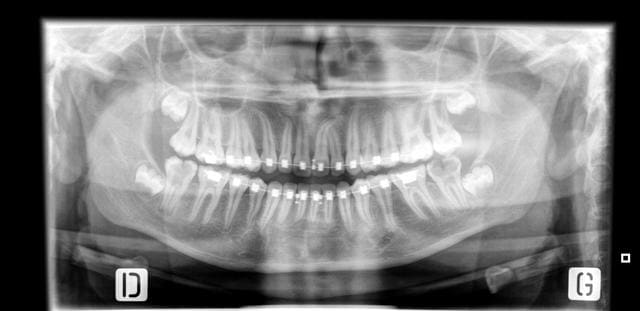

Faut-il conserver ces 37 et 47 ?

je proposerai la mise en place des 8 ... sans hésiter mais il faut la coopération d'un odf ...

Il y a quand même un gros soupçon de MIH, ne tapez pas sur les orthos les dents étaient peut être déjà comme ça avant même de sortir.

Bye bye les 7.

Vire les 7

Elle ont des racines côniques et trop trop délabrées

Mieux vaut encore essayer de laisser les 8 les remplacer

Je vois que mon plan de traitement proposé à la patiente semble suivi par tous.

Virer 37 et 47 et espérer que les 38 et 48 vont développer de belles racines...

Si tu vires 37 et 47, comment comptes-tu empêcher l'égression de 17 et de 27 qui se retrouveront sans antagoniste ?